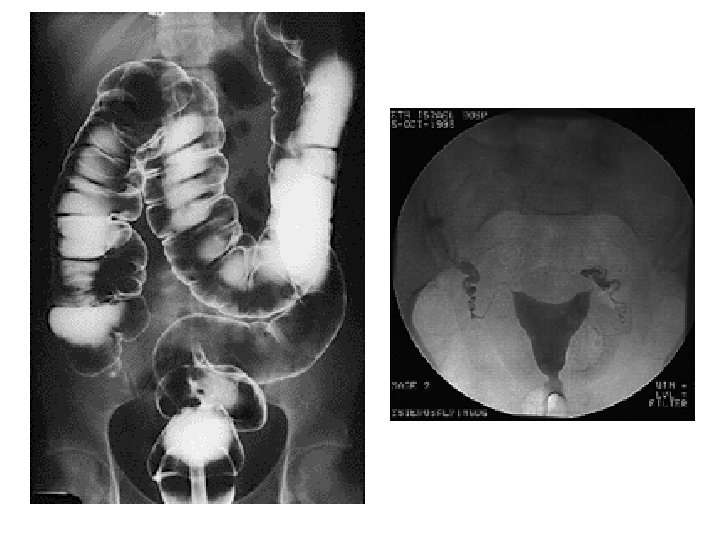

Fluoroscopy 22

TECHNOLOGIST • FLUOROSCOPY • Dawn Charman RT (R), (F) • CONTRAST MEDIA (X-RAY DYE)

Types of Diagnostic Exams • • • Chest Extremities Skull/ Facial Spine Gastrointestinal Interventional 15